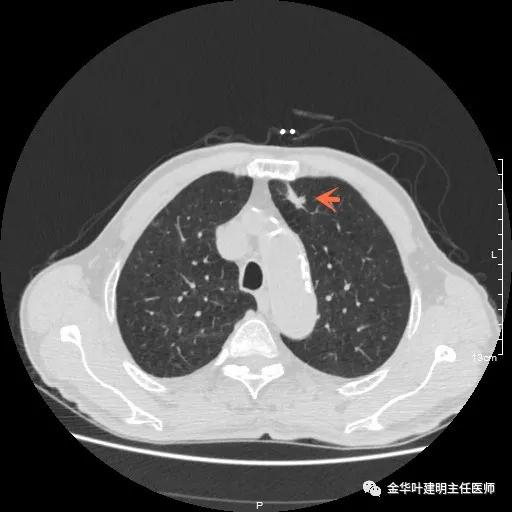

以上示右肺中叶病灶3。是混合磨玻璃结节,位置差,邻近肺门部,无法局部楔形切除,抗炎治疗后靶扫描显示了更清楚的细节,是典型的肺癌影像特征(此处未另提供)。从单病灶来看,需要行右肺中叶切除并清扫淋巴结才能得以治疗。